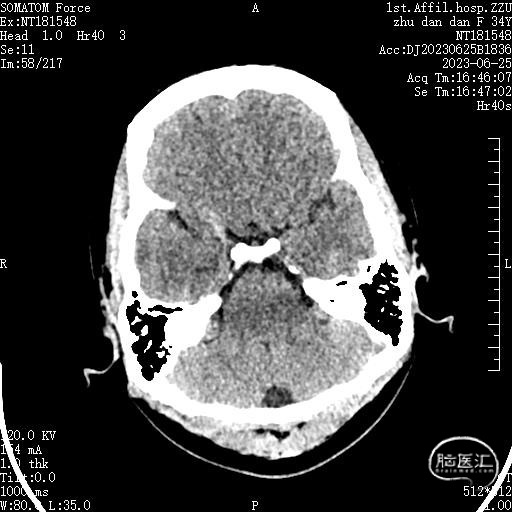

MRI:可见左侧椎动脉和小脑前下动脉压迫面神经REZ区

术前MRI:可见面神经REZ区有血管影,但是其信号与动脉信号有区别。同时因后颅窝解剖结构变异,乙状窦位置可能影响CPA区暴露